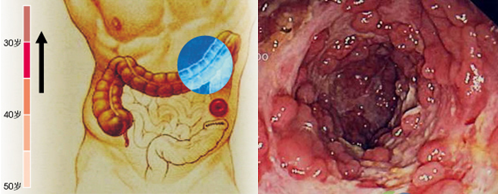

直腸息肉圖片

A:直腸息肉早期臨床症狀常不明顯,而且部分患者沒有任何的臨床表現,大多是在體檢或者檢查其他疾病時,從而發現,隨著直腸息肉的增大,其臨床上可能會出現表現,比如大便中帶血,常常是無痛性的便中帶血,出血量比較少。主要是因為直腸息肉表面出現糜爛,糞便通……

A:直腸息肉的主要症狀有大便帶血,出血一般都為鮮紅色的。如果息肉伴有潰瘍,會出現粘液性血便,還有腹痛、腹脹、便秘和腹瀉交替出現的情況。息肉如果較多、時間較長的患者會有貧血、消瘦、乏力的情況。如果發現大便習慣改變,並有腹痛,便血的情況一定要去正規……

A:直腸息肉是指直腸粘膜向腸腔內突出打一種贅生物,主要生長在直腸的下端,可分為炎症性,增生性,腺瘤性,在兒童最為常見,與環境因素以及遺傳因素有關,最常見的臨床表現便是便血,患者一般沒有疼痛感,大便帶血呈鮮紅色,少數患者還會有腹痛腹瀉等症狀,一般……

A:直腸息肉是指直腸內粘膜腸腔內的突出隆起性的病變,一般可分為炎症性,增生性或者是腺瘤性息肉三種,增生性息肉或者炎症性息肉可能與感染因素或者是損傷因素有關係,而腺瘤性息肉可能與環境因素和遺傳因素有關,能夠發生癌變。炎症性和增生性息肉不會發生癌變……